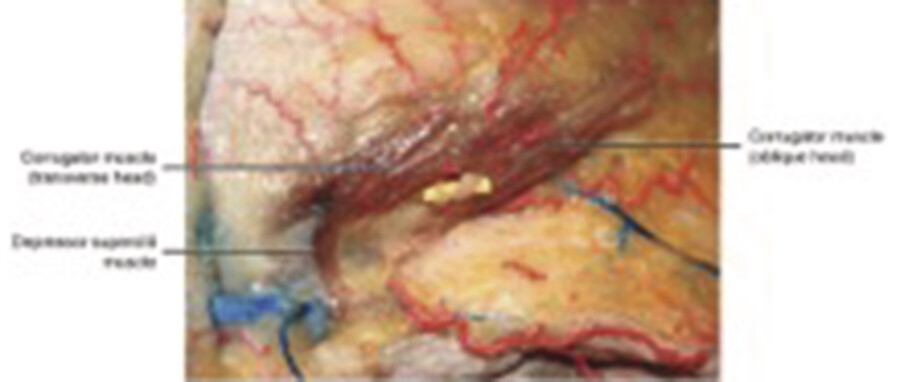

In cadaver dissections by Pessa, the corrugator muscle was identified with two muscular bellies, a transverse and an oblique (Fig. 3.4). 8 The thickest portion of the muscle is at the medial canthus. Substantial bulk was still present at the midpupillary line, but no distinct corrugator fibers were detectable at the lateral canthus. 7

Depressor Supercilii

The small, vertically oriented depressor supercilii muscle originates on the medial orbital rim, near the lacrimal sac, and inserts on the medial aspect of the bony orbit, inferior to the corrugators (Fig. 3.5). It acts as an accessory depressor of the medial eyebrow. 6 Of note, not all reports have identified this muscle.